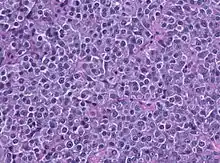

A prolactinoma is a tumor (adenoma) of the pituitary gland that produces the hormone prolactin. It is the most common type of functioning pituitary tumor.[1] Symptoms of prolactinoma are due to abnormally high levels of prolactin in the blood (hyperprolactinemia), or due to pressure of the tumor on surrounding brain tissue and/or the optic nerves. Based on its size, a prolactinoma may be classified as a microprolactinoma (<10mm diameter) or a macroprolactinoma (>10mm diameter).